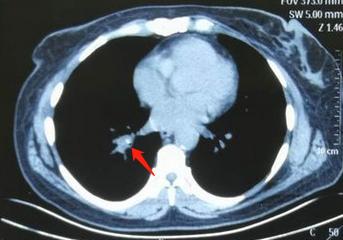

请支气管镜室出面帮忙,钳取骨头一块,都发黑了:

本病例来自网友七彩神仙